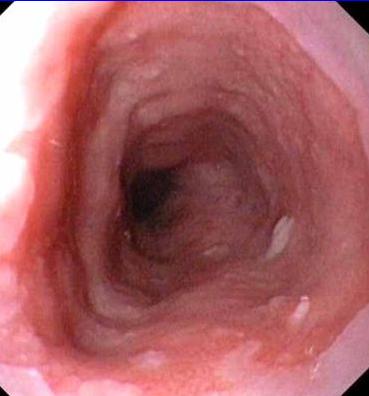

Images fibroscopie normale a la jonction de la muuese

gastriue et muueuse oesophagien |